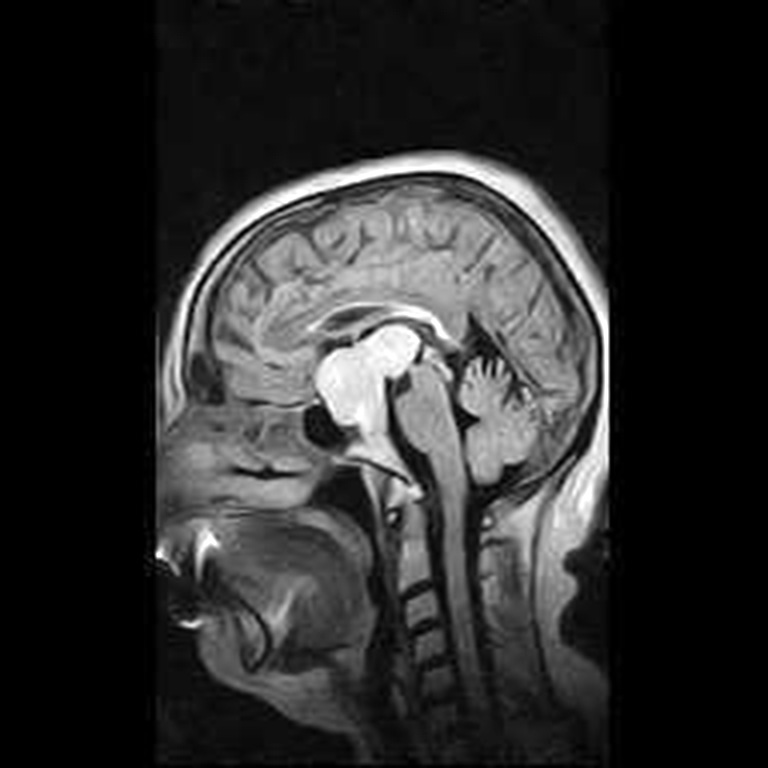

Fig. 2. Patient P., 64 years old, HIPA with suprasellar extension, central chiasmal position. Brain MRI: A – coronal projection; B – sagittal projection

A B